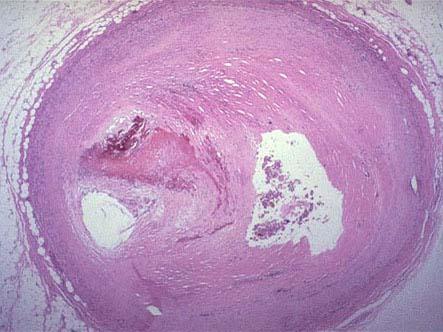

问题 图1示冠状动脉粥样硬化伴血栓形成,图2为血栓干燥收缩,新鲜肉芽组织取代之,这种现象称 ( )

选项 A.血栓钙化 B.血管壁肉芽肿形成 C.血栓溶解、吸收 D.血栓机化、再通 E.以上都不是

答案 D